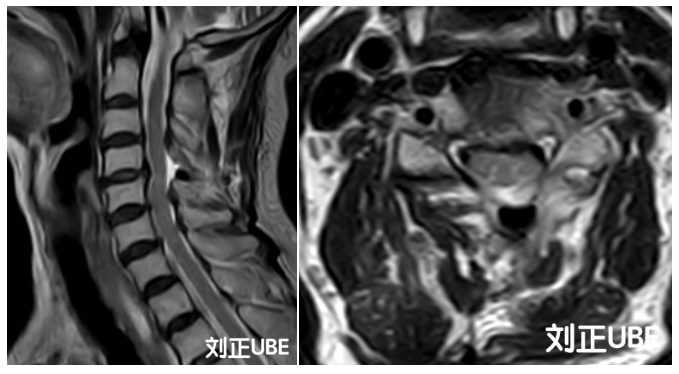

一位80岁的女性患者 , 由于黄韧带肥厚等组织压迫脊髓 , 产生明显行走不稳、下肢踩棉感等症状 , 经查确诊为脊髓型颈椎病 , 脊髓压迫主要位于颈4-5节段 。

患者术前颈椎MRI提示颈4-5节段颈脊髓受压伴髓内信号改变